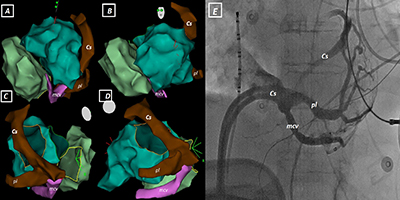

The Last Exit Before the Bridge to Epicardium in Ventricular Tachycardia Ablations: Coronary Venous System